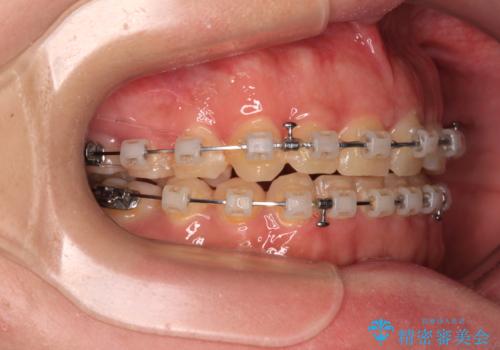

- クリアブラケット

口元の突出感は強くなかったため非抜歯矯正での対応となりますが、捻転を改善する際に上顎前歯が前突する可能性があったため、上顎臼歯部にアンカースクリューを使用して、歯列が前方に転位しないようにすることとしました。

ワイヤー矯正でもインビザラインでも対応可能でしたが、上顎歯列が前方位であるときには、ワイヤー矯正の方がより良い仕上がりとなる可能性が高いため、ワイヤー矯正をおすすめいたしました。